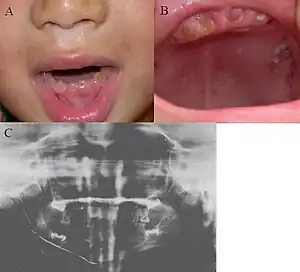

| Oral photographs from an individual with Dentinogenesis imperfecta | |

Dentinogenesis imperfecta (DI) is a genetic disorder of tooth development. This condition is a type of dentin dysplasia that causes teeth to be discolored (most often a blue-gray or yellow-brown color) and translucent giving teeth an opalescent sheen.[1] Although genetic factors are the main contributor for the disease, any environmental or systemic upset that impedes calcification or metabolisation of calcium can also result in anomalous dentine.

Consequently, teeth are also weaker than normal, making them prone to rapid wear, breakage, and loss. These problems can affect both primary (deciduous) teeth and permanent teeth. This condition is inherited in an autosomal dominant pattern, as a result of mutations on chromosome 4q21, in the dentine sialophosphoprotein gene (DSPP).[2] It is one of the most frequently occurring autosomal dominant features in humans.[3] Dentinogenesis imperfecta affects an estimated 1 in 6,000 to 8,000 people.

Clinical appearance is variable with presentation ranging from gray to yellowish brown, but the characteristic feature is the translucent or opalescent hue to the teeth.